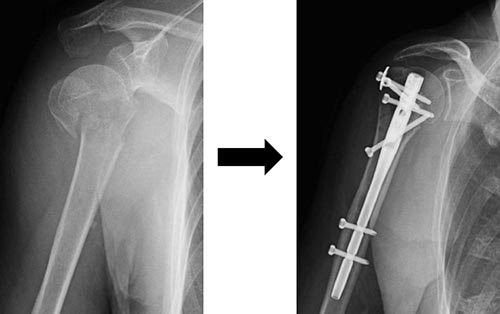

手術方法は、骨接合術は髄内釘固定法(図3)やロッキングプレート固定法(図4)が行われます。脱臼骨折の場合には、人工骨頭置換術が行われる場合もあります(図5)。近年リバース型人工肩関節置換術も用いられるようになり、臨床成績が安定しています(図6)。

図3 髄内釘固定法